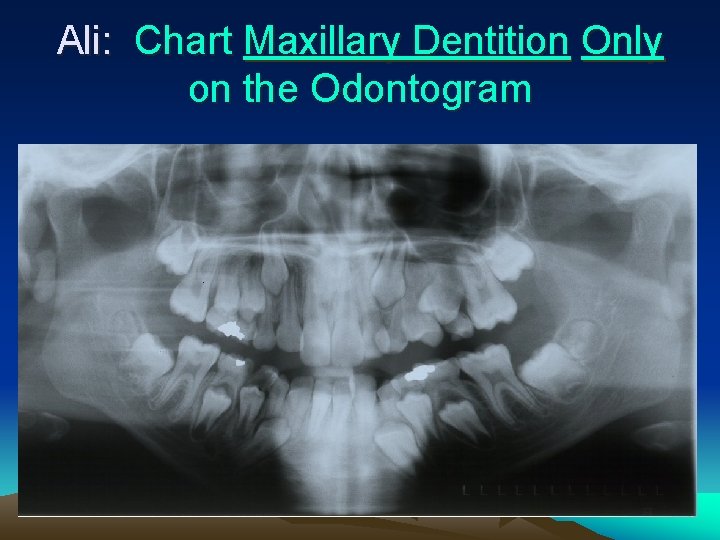

Ali: Chart Maxillary Dentition Only on the Odontogram

Ali’s Bite Wings • Chart any pathology or abnormal findings (including caries) for the maxillary arch only on the odontogram.

Ali • Teeth Present: #3, A, B, C, 7, 8, 9, 10, H, 12, J, 14 • Restorations: #A-MO, #B-DO. • Pathology/Caries: #3 -M; #A-D; #B-M; #H-D; #J-abscess, #14 -MO Note: #6 and #11 very advanced root development.

Ali

Ali Tx Plan • Extract all maxillary primary teeth – #A, B, J- Multiple caries and near exfoliation – TE #C and #H due to root formation #6 and #11 • Restore #3 with direct M composite • Restore #14 -MO • Place Nance Space Maintainer- slight space deficiency, but this will be very beneficial.

Ali Tx Sequence • Appt 1 – Fit bands #3 and #14 and Impress for Nance – Restore #14 – TE #H and #J • Appt 2 – Restore #3 – Seat Nance – TE # A, B, C